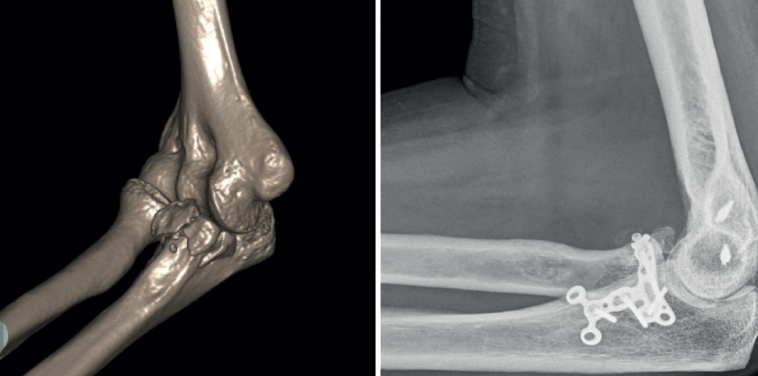

- Tipo III. Las fracturas basilares grandes suelen formar parte de una fractura-luxación del olécranon; por tanto, en todos los casos precisarán tratamiento quirúrgico. Podremos sintetizarlas directamente con un tornillo desde la placa posterior de osteosíntesis del cúbito y añadir tornillos interfragmentarios o canulados si es necesario (Figura 6). La reducción de los fragmentos conviene hacerla de forma secuencial, preferiblemente de distal a proximal. A veces precisan una placa medial adicional. Si hay un único fragmento grande, también se pueden fijar con un tornillo insertado de anterior a posterior.